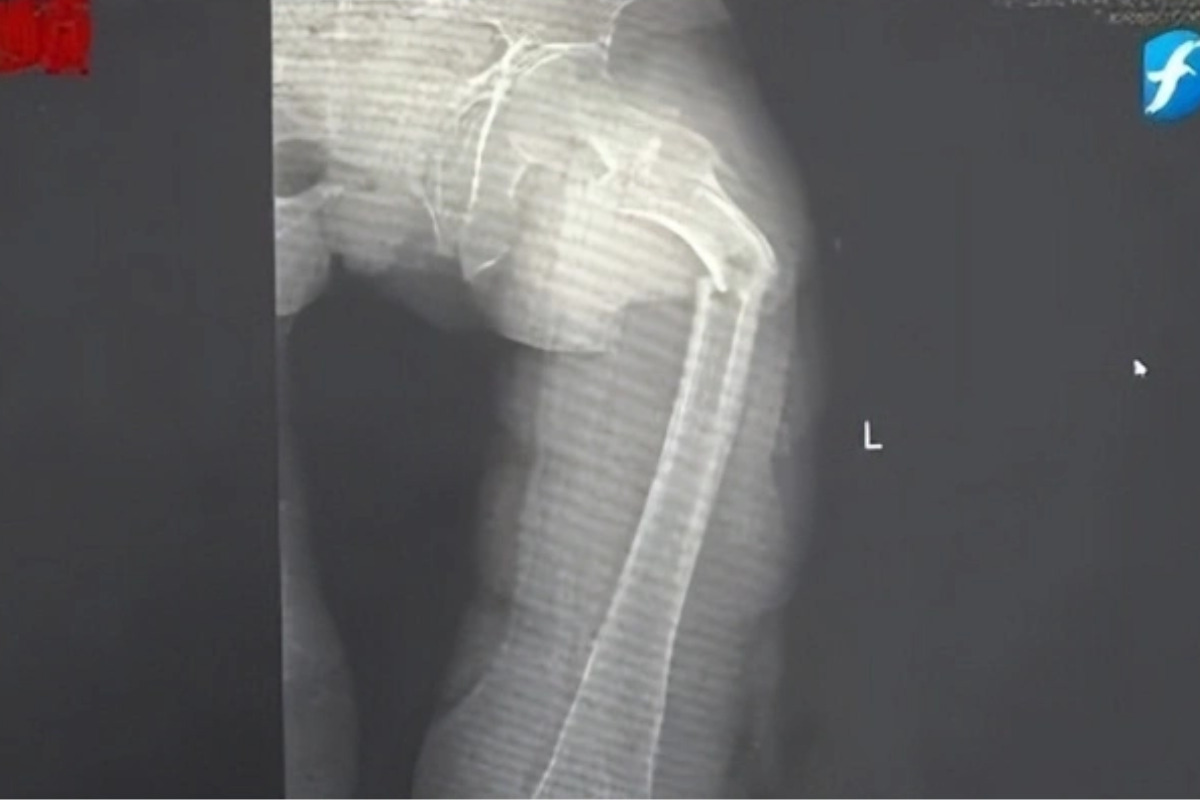

Đến nửa đêm, anh Cung bị giật mình tỉnh giấc vì cơn đau ở đùi. Anh phát hiện ra mình không thể đi lại được nhưng cố chờ đến trời sáng hẳn rồi nhờ người nhà đưa đi bệnh viện. Kết quả chụp X-quang tại Bệnh viện Nhân dân số 2 Phúc Kiến (Trung Quốc) khiến anh Cung sốc nặng: xương đùi trái của anh bị gãy làm hai mảnh.

Ngoài 30 tuổi xương đã "xốp như tổ ong", ho cũng gãy xương đùi vì mê loại nước "ngòn ngọt", uống tê đầu lưỡi - Ảnh 2. Hình ảnh xương đùi bị gãy đôi vì loãng xương sớm của anh Cung